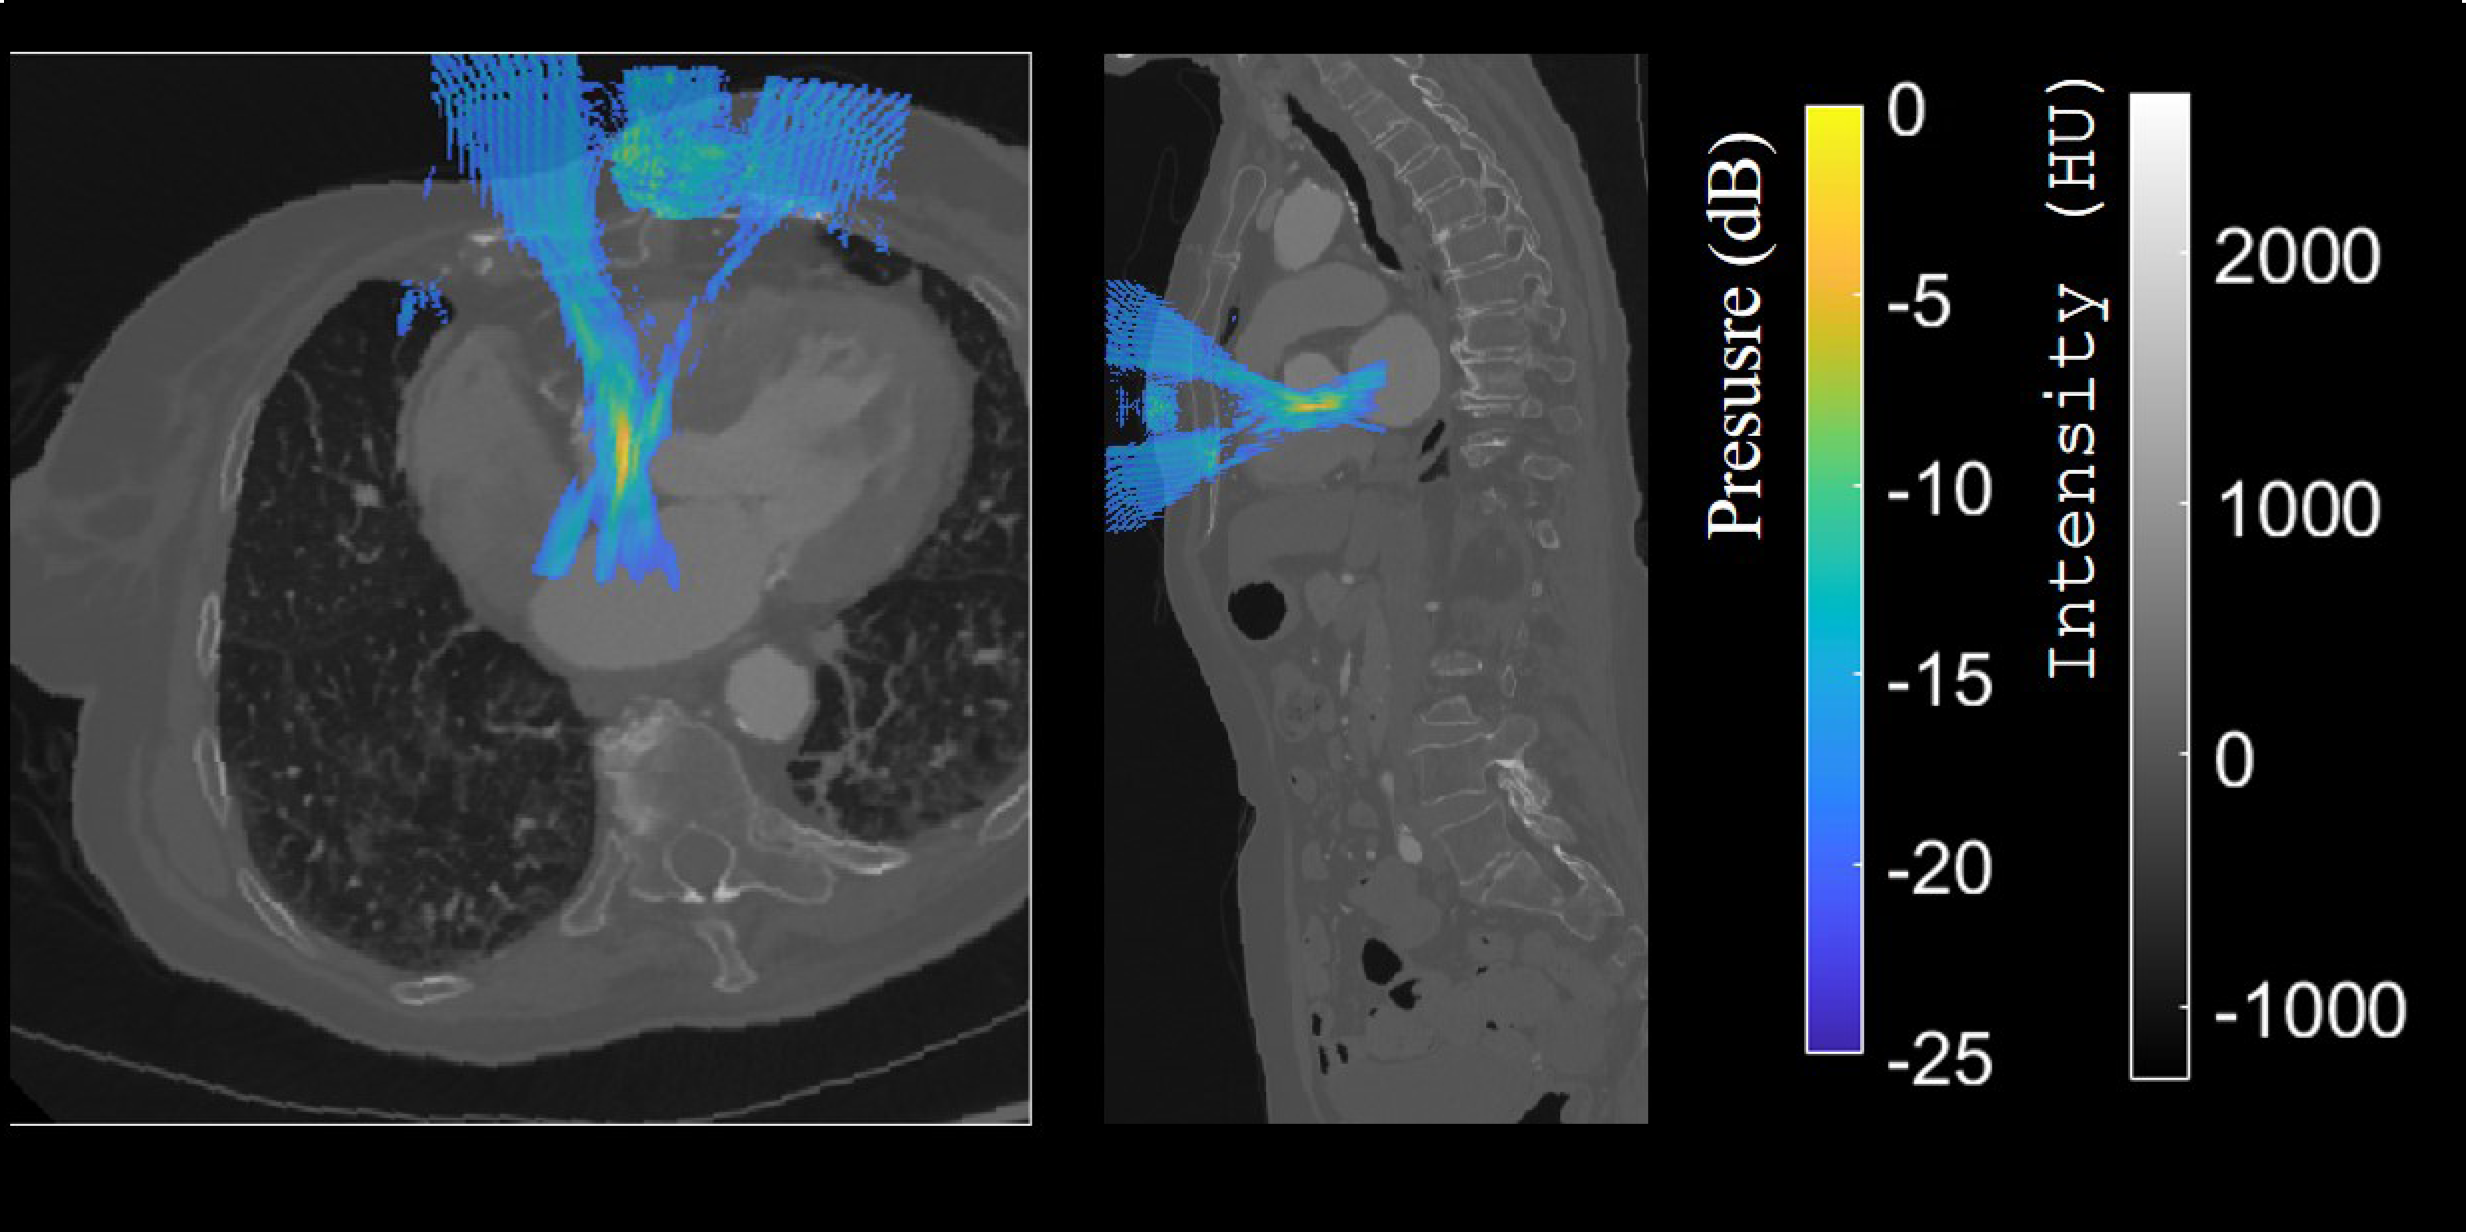

- extracorporal therapy of congenital heart defects in children, using ultrasound waves applied from the outside of the body to remotely treat the heart,